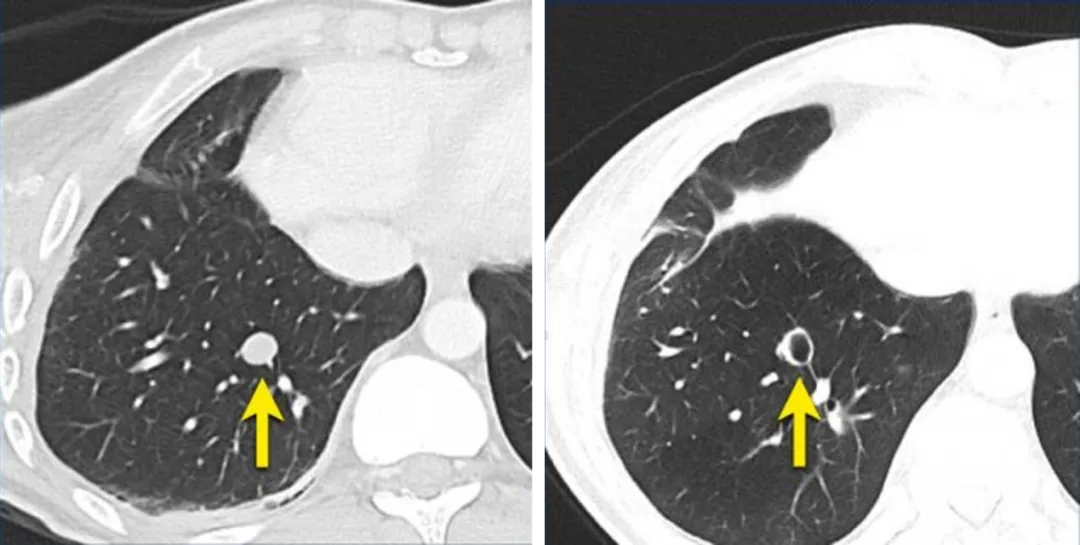

在基线时,右侧肺癌最长直径大于10mm,选作靶病灶,在后续访视病灶长径减小,

但边界不清晰,记录测量值时默认为5mm。